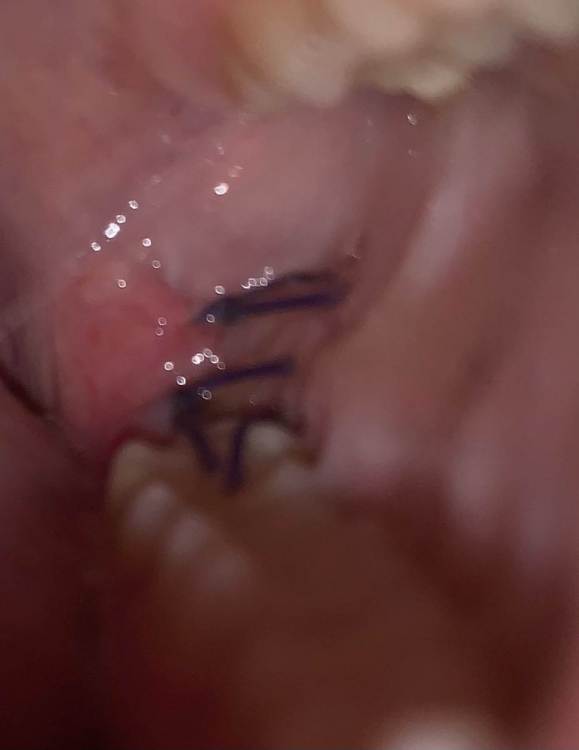

Nadezda79 Опубликовано 22 марта, 2022 Автор Поделиться Опубликовано 22 марта, 2022 (изменено) Здравствуйте! На данный момент имеются периодические ноющие боли в соседних зубах, а так же чувство распирания в седьмом зубе. Боли терпимые, не требуют приема анальгетиков, но всё же беспокоят. Дискомфорт со стороны удаленного зуба при глотании. Температуры нет. Швы были сняты на седьмой день. Сегодня, на десятый день, была на осмотре у другого стоматолога по поводу болей, к хирургу, проводившему удаление, возможности попасть нет. При осмотре десна вокруг лунки болезненная. Со слов врача имеется небольшой сгусток на дне лунки, при сохранении болей в течении нескольких дней следует провести повторно кюретаж. И собственно вопрос, нормально ли сохранение болей в течении такого времени после удаления? Или действительно есть необходимость повторно создавать сгусток. Изменено 22 марта, 2022 пользователем Nadezda79 Ссылка на комментарий